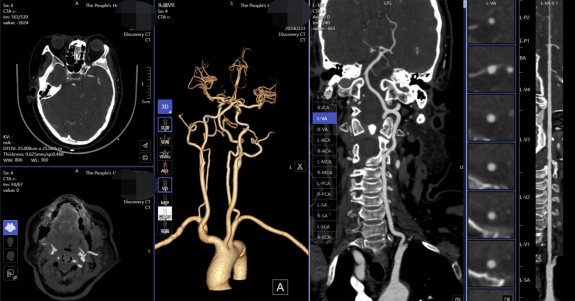

(一)腦卒中“一站式”CT檢查,包括CT平掃(NCCT),CT血管成像(CTA)和CT灌注成像(CTP),成像方法簡便,3-5分鐘即可完成檢查。只需一次檢查即可完成腦卒中治療前評估,為患者得到及時有效的治療提供有力支持。

圖片

腦卒中“一站式”CT檢查